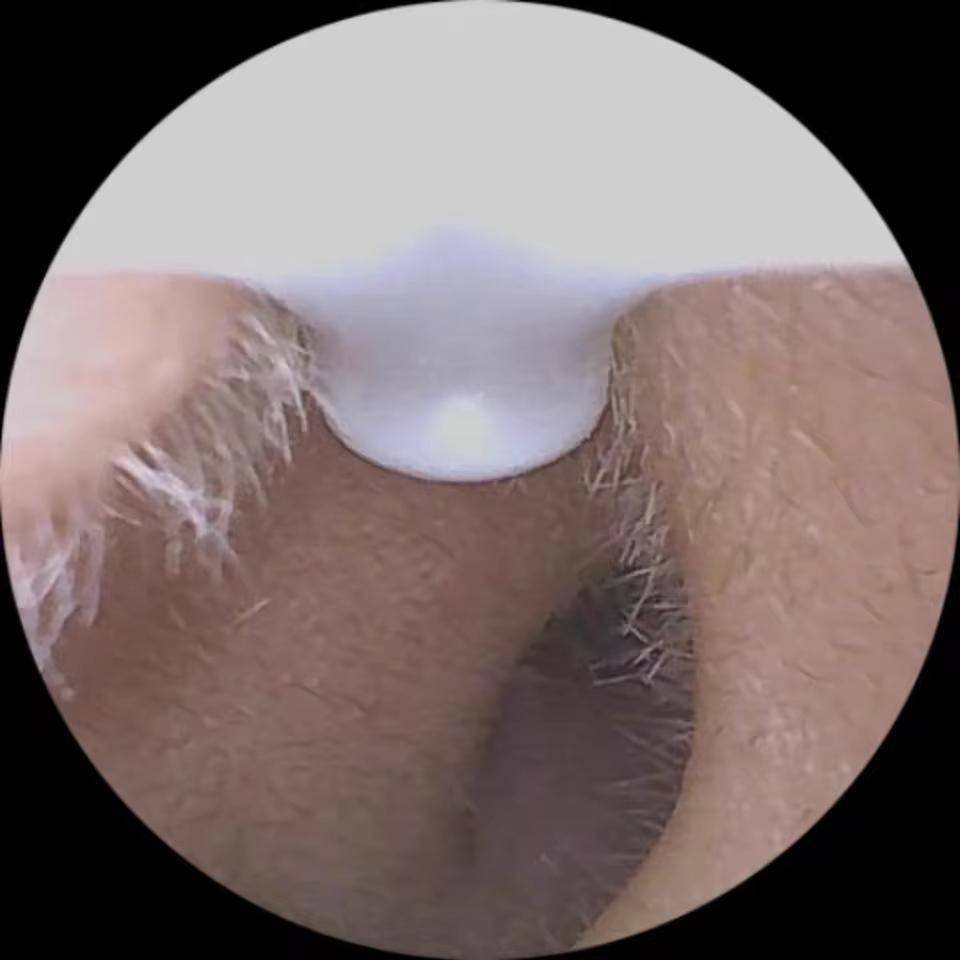

Camear е идеалният инструмент за всички, които търсят модерен, прецизен и лесен за употреба ушен чистач! Използването му е истинска детска игра. Благодарение на вградената си камера с висока разделителна способност, можете да видите вътрешността на ухото си в реално време директно от смартфона си, за безопасно и перфектно почистване. Меката силиконова накрайник осигурява оптимален комфорт и предотвратява всякакво дразнене. Независимо дали е за лична или семейна употреба, Camear предлага практичен, хигиеничен и напълно безопасен опит.

Camear ви осигурява перфектна хигиена и пълен контрол по всяко време.

Прецизно почистване и максимална хигиена

Наблюдавайте вътрешността на ушите си дори в тъмното.